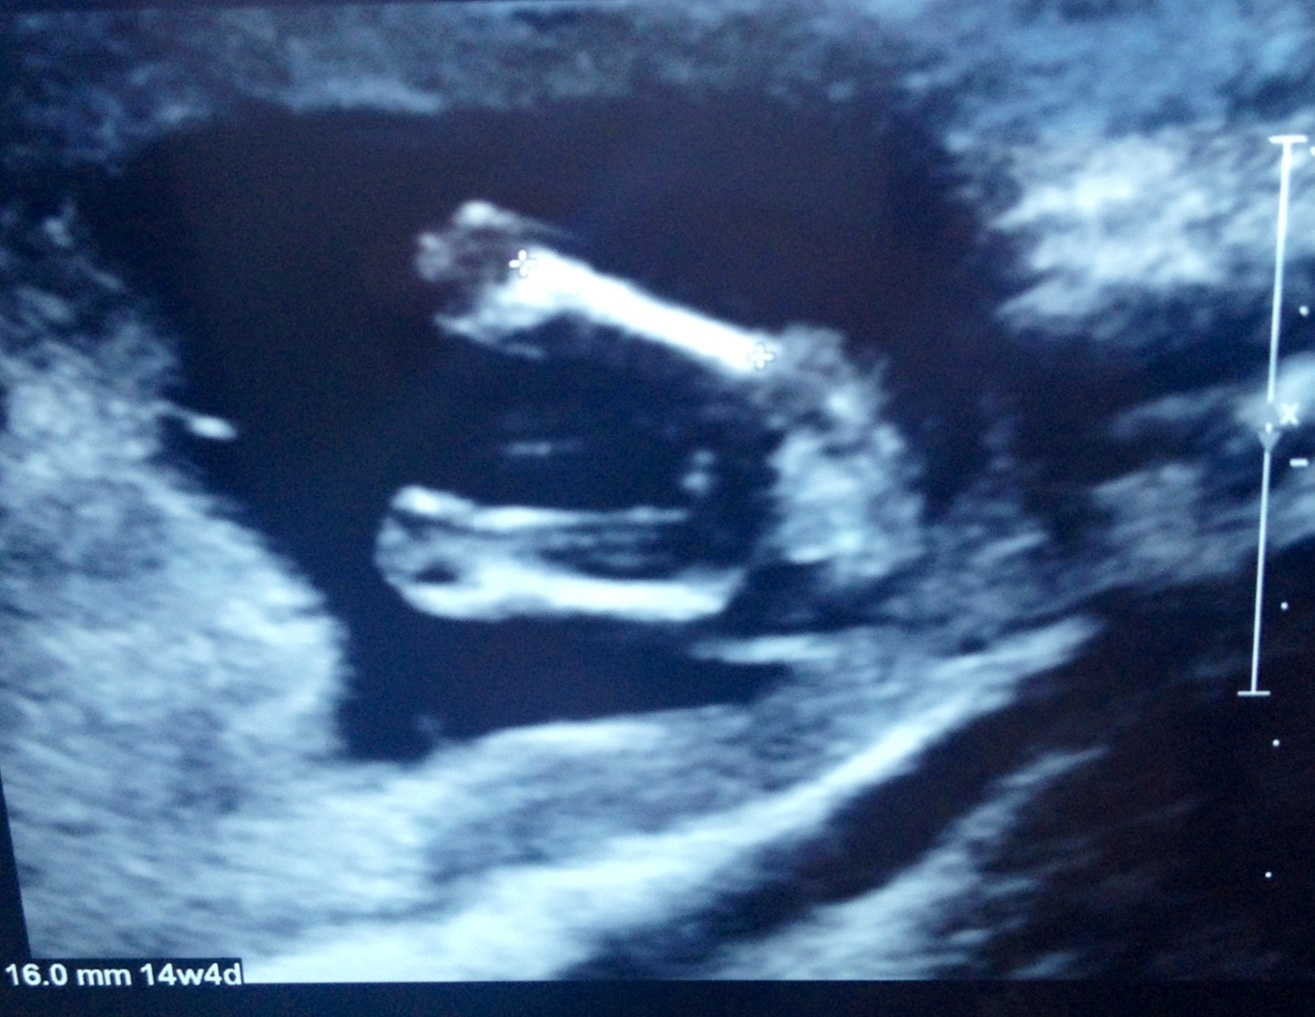

Here are my 14 week 5 day (my dates went back to normal dates) potty shots.. Tech did close up while doing scan and showed me baby had three lines and she thought it was a girl, and then said to not take that as a confirmed girl till 20 weeks!! What do you all think?